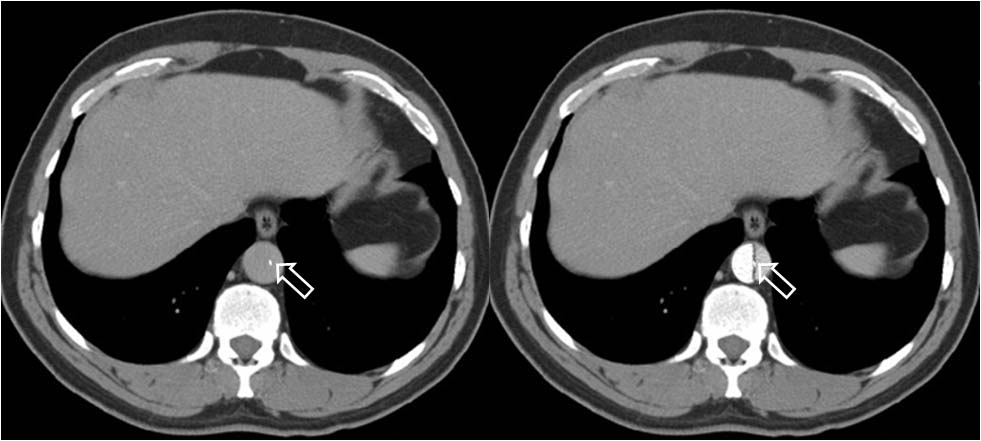

SIGNO DEL DESPLAZAMIENTO DEL CALCIO INTIMAL

Signo de disección aórtica en la TC. Consiste en la presencia de una placa de calcio desgajada de la pared aórtica, acompañando al colgajo intimal. El signo se ha descrito en la placa simple (hay un ejemplo magnífico en http://www.wikiradiography.net/page/Calcium+Sign) y en la TC. En la imagen de la izquierda vemos la TC sin contraste mostrando el calcio intimal desplazado (flecha). El angioTC permite ver el flap intimal -con el calcio (flecha)- y la doble luz aórtica.

Izquierda: aorta normal. Centro: aorta arteriosclerótica con pared engrosada y placas de ateroma calcificadas. Derecha: En la disección aórtica, el desplazamiento de la capa íntima se acompaña de la placa calcificada, lo que explica el signo.